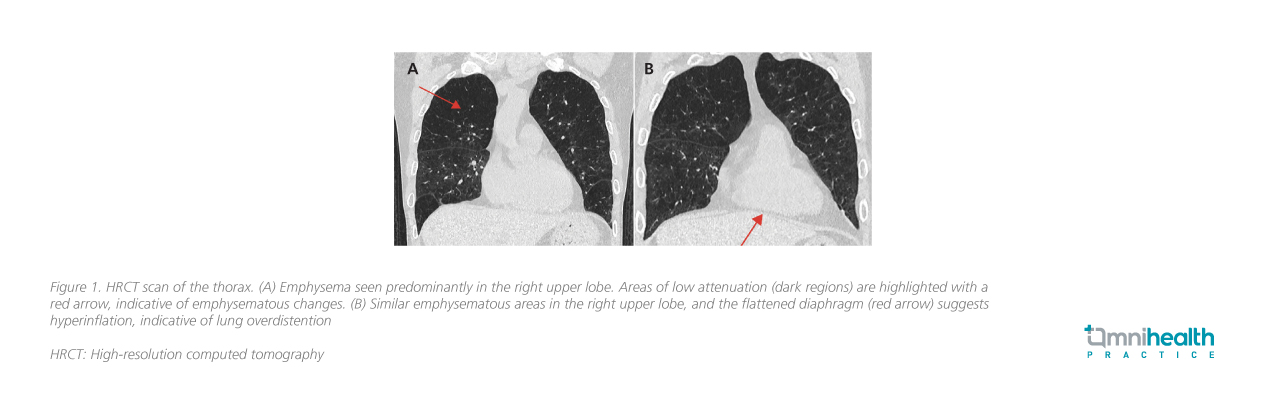

High-resolution CT (HRCT) of the thorax demonstrated severe emphysematous destruction, predominantly affecting the upper lobes (figure 1). InterVapor CT protocol and IP3 analysis identified the right upper lobe—specifically the RB1 and RB3 bronchopulmonary segments—as the most diseased, with disease severity scores of 59% and 46%, respectively.